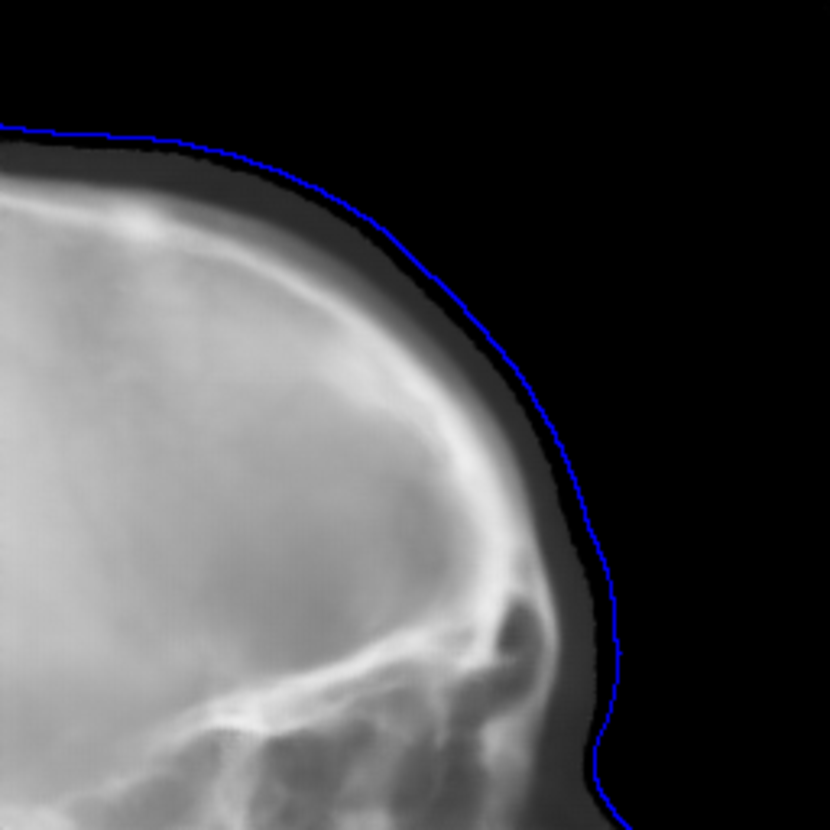

The SR techniques are also applied to synthetic cephalograms. The results of one Type I synthetic cephalogram example are displayed in Fig. 14. To visualize details better, an ROI patch is chosen for each method, whose position is marked in Fig. 14(a). Consistent with the results on the ISBI test patches, the patches of ESRGANRDB and ESRGANRRDB using LR patches as the input also suffer from checkerboard artifacts in Figs. 14(h) and (j). In addition, some undesired bright/dark artifacts occur in Fig. 14(j). In Figs. 14(i) and (k), apparent jagging artifacts are no longer observed for ESRGANRDB and ESRGANRRDB using ILR patches as the input, since the edges in the bicubic interpolation patches are smooth without jaggies. As expected, the patch predicted by pix2pixGAN has realistic appearance without the introduction of jagging nor checkerboard artifacts. Due to its superior performance to ESRGANRDB and ESRGANRRDB using ILR on the ISBI test patches, in this work we choose pix2pixGAN as the SR method.